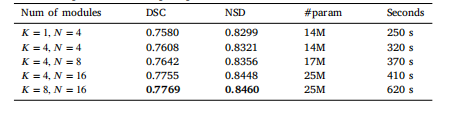

Table 4Ablation studies of Hyper-parameter. We present the performance across aspectrum of Hyper-parameters, alongside metrics of parameter count, as wellas the computational time per epoch.

表4 超参数消融实验 我们展示了不同超参数配置下的模型性能,同时提供了参数数量指标以及每个训练轮次(epoch)的计算时间。